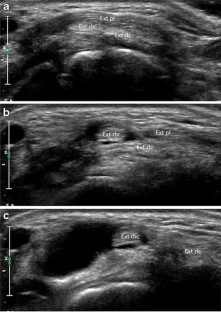

Intersection syndrome: ultrasound imaging

Intersection syndrome was identified in 1.9 % of all patients evaluated in the setting of a specialized hospital. Ultrasound is a non-invasive, simple, and economical method for the identification of intersection syndrome, tendon sheath anatomy (individual or separate sheaths) and to exclude other pathological conditions.